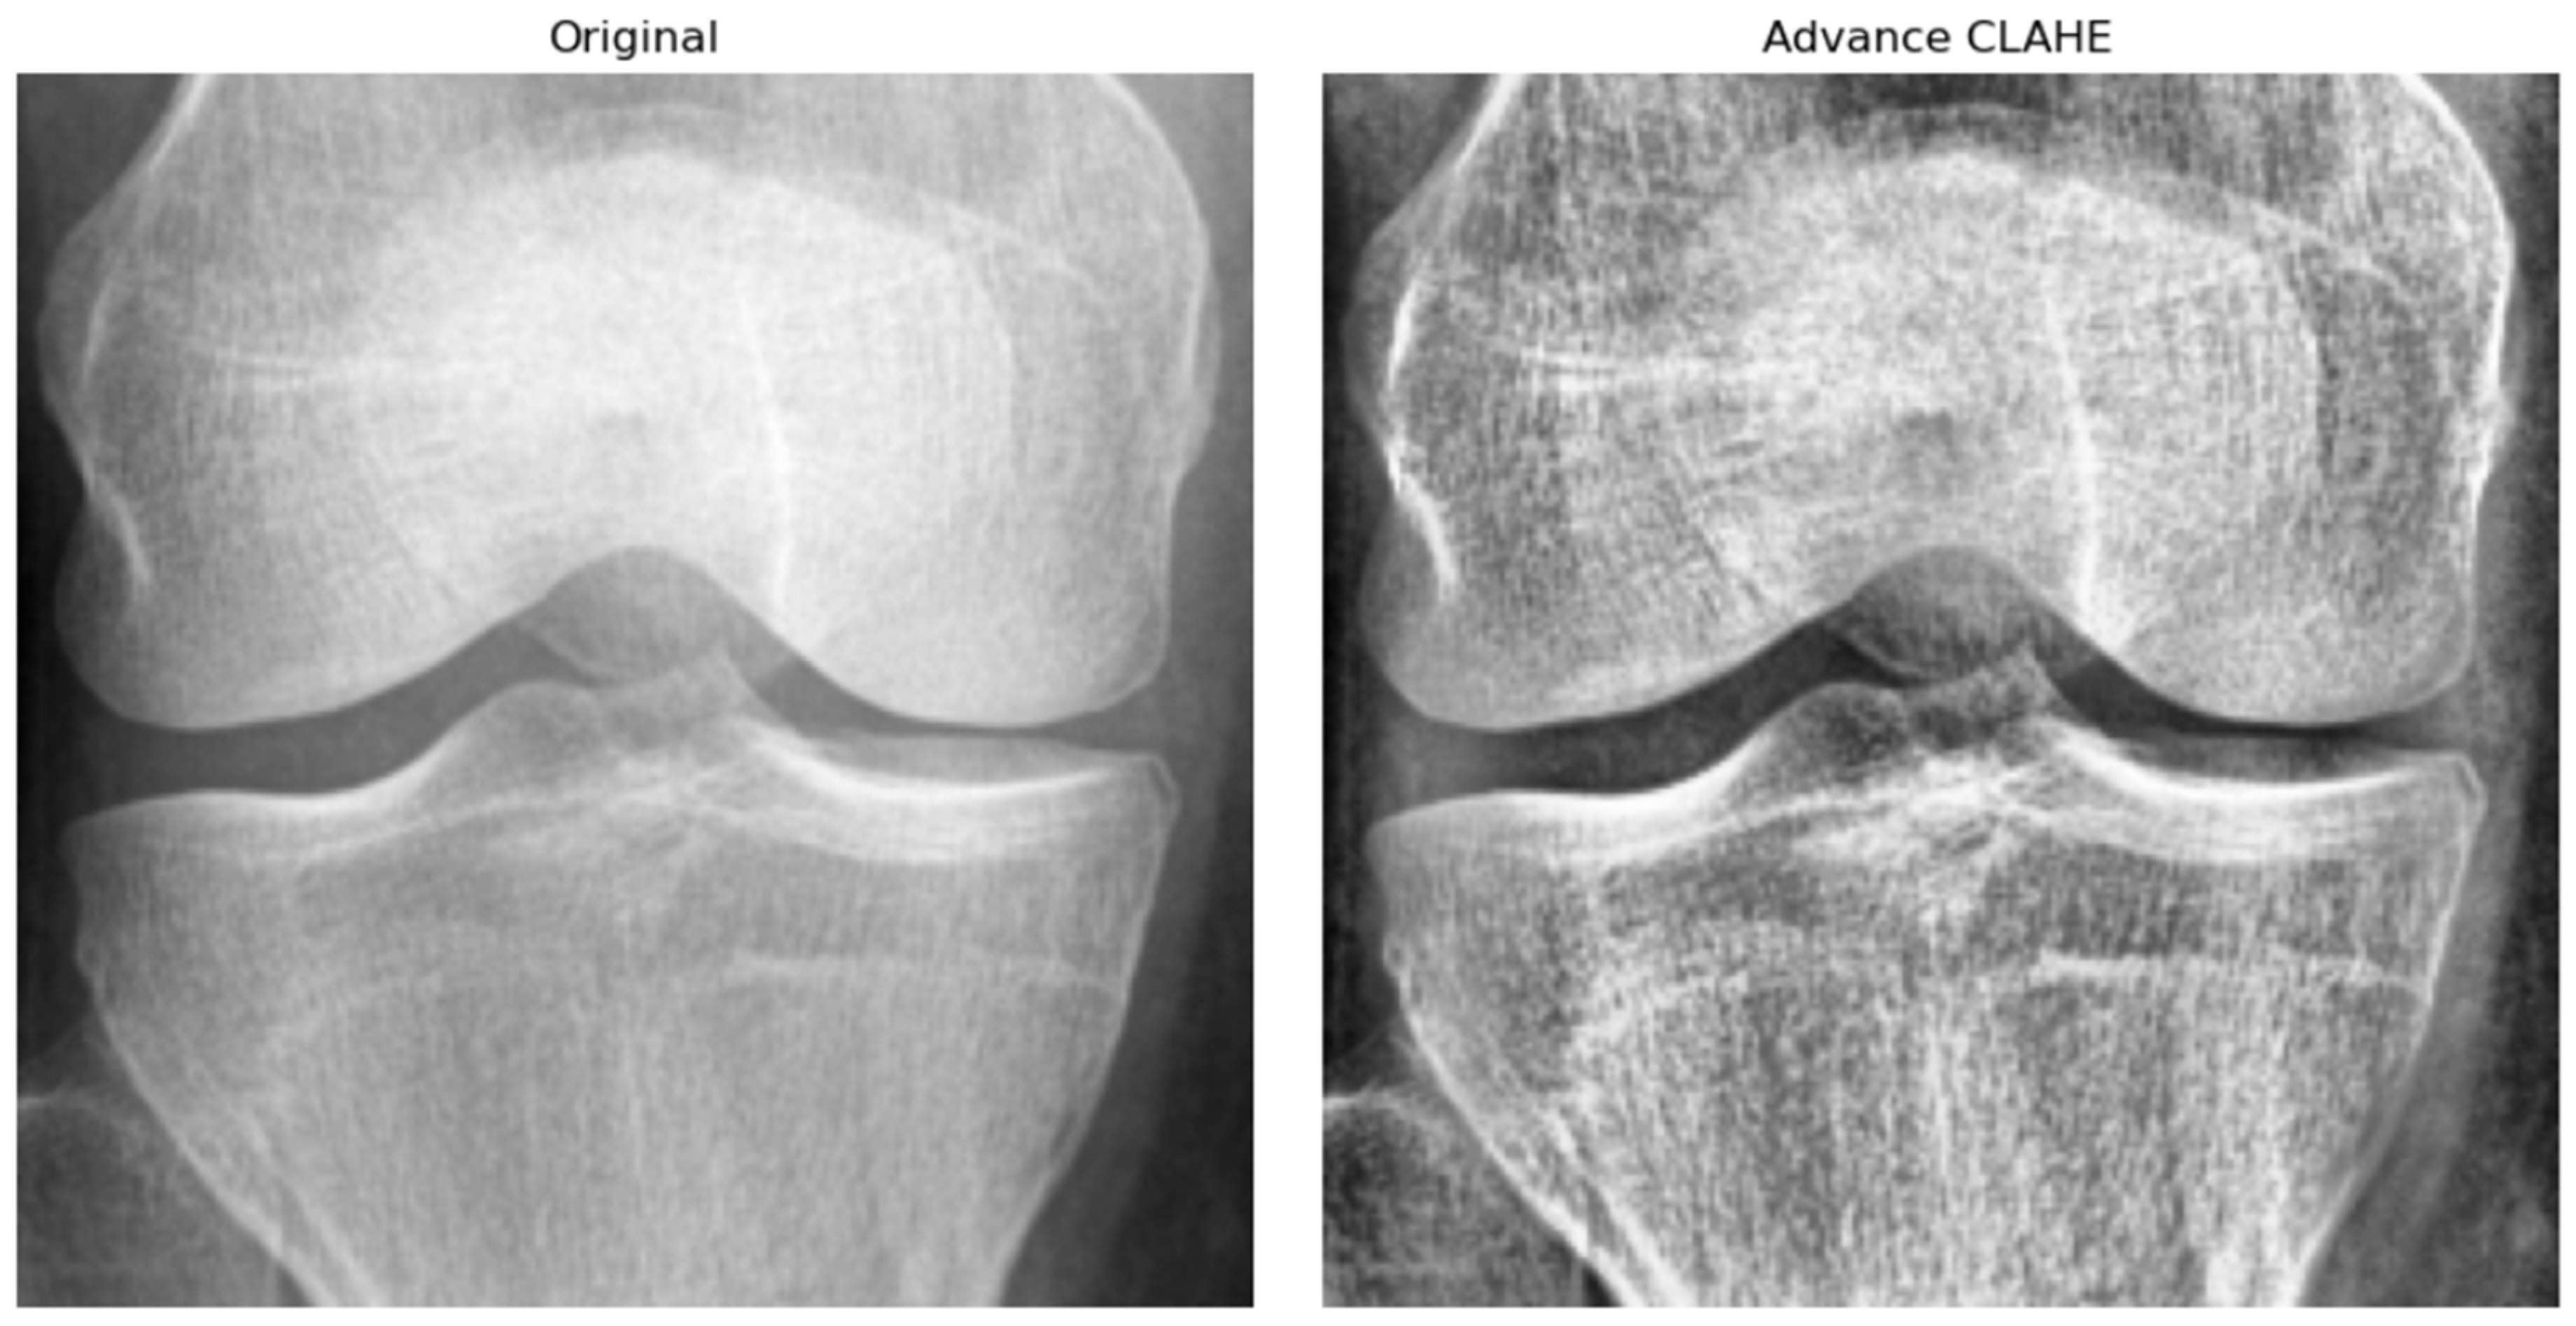

Prior to training the Knee-DNS model, a series of data preprocessing steps were applied to enhance the quality and uniformity of the X-ray images. First, all the images were resized to a fixed resolution of 700 × 600 pixels to standardize input dimensions and reduce computational complexity. Subsequently, advanced contrast-limited adaptive histogram equalization (CLAHE) was applied to improve local contrast and highlight structural details relevant to KOA diagnosis, as shown in Figure 6. To suppress noise and smooth the images, Gaussian filtering was employed. Furthermore, all pixel intensities were normalized to the [0, 1] range, which helped stabilize the training process by ensuring consistent input distributions. Lastly, data augmentation techniques, such as random rotation, horizontal flipping, and zooming, were applied to improve model robustness and prevent overfitting by exposing the network to a wider variety of plausible anatomical presentations.

Figure 6. A visual example of image preprocessing using the advanced CLAHE technique.